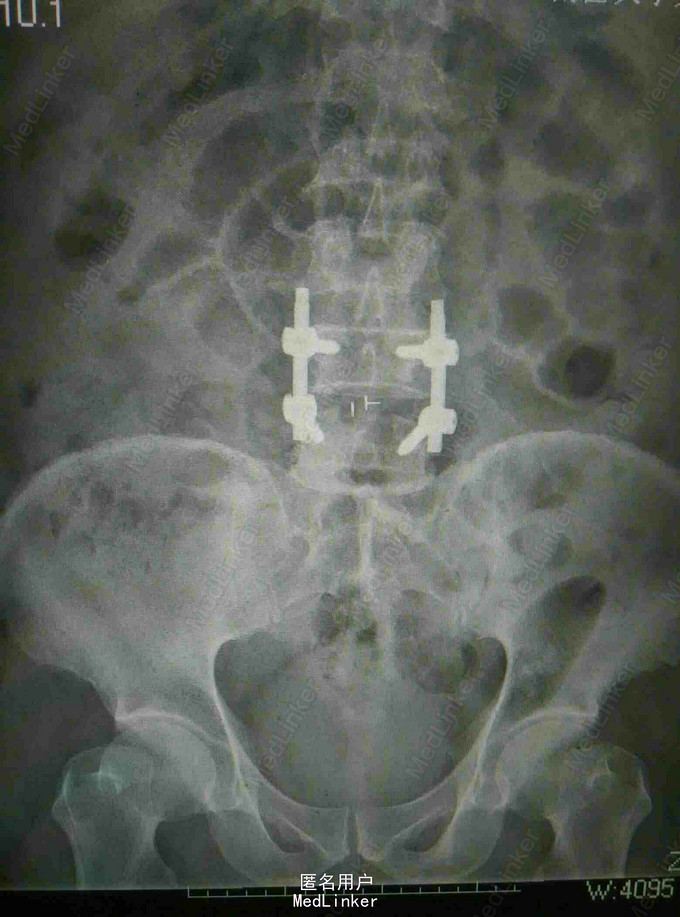

诊断:腰椎间盘突出 马尾神经受压 双下肢不全瘫 治疗:腰椎后路减压植骨融合内固定术

随访:嘱三周后可佩戴腰围下地活动,卧床加强腰背肌肉锻炼,定期复查。 讨论:患者腰椎间盘突出症反复四年,未予重视,无特殊处理,遂进展为大小便障碍,双下肢不全瘫,此时即使手术效果也很差,神经功能恢复困难,典型小病拖大,错失时机。因此对出现下肢症状的患者建议早期手术,一旦进展出现大小便障碍则错失机会。